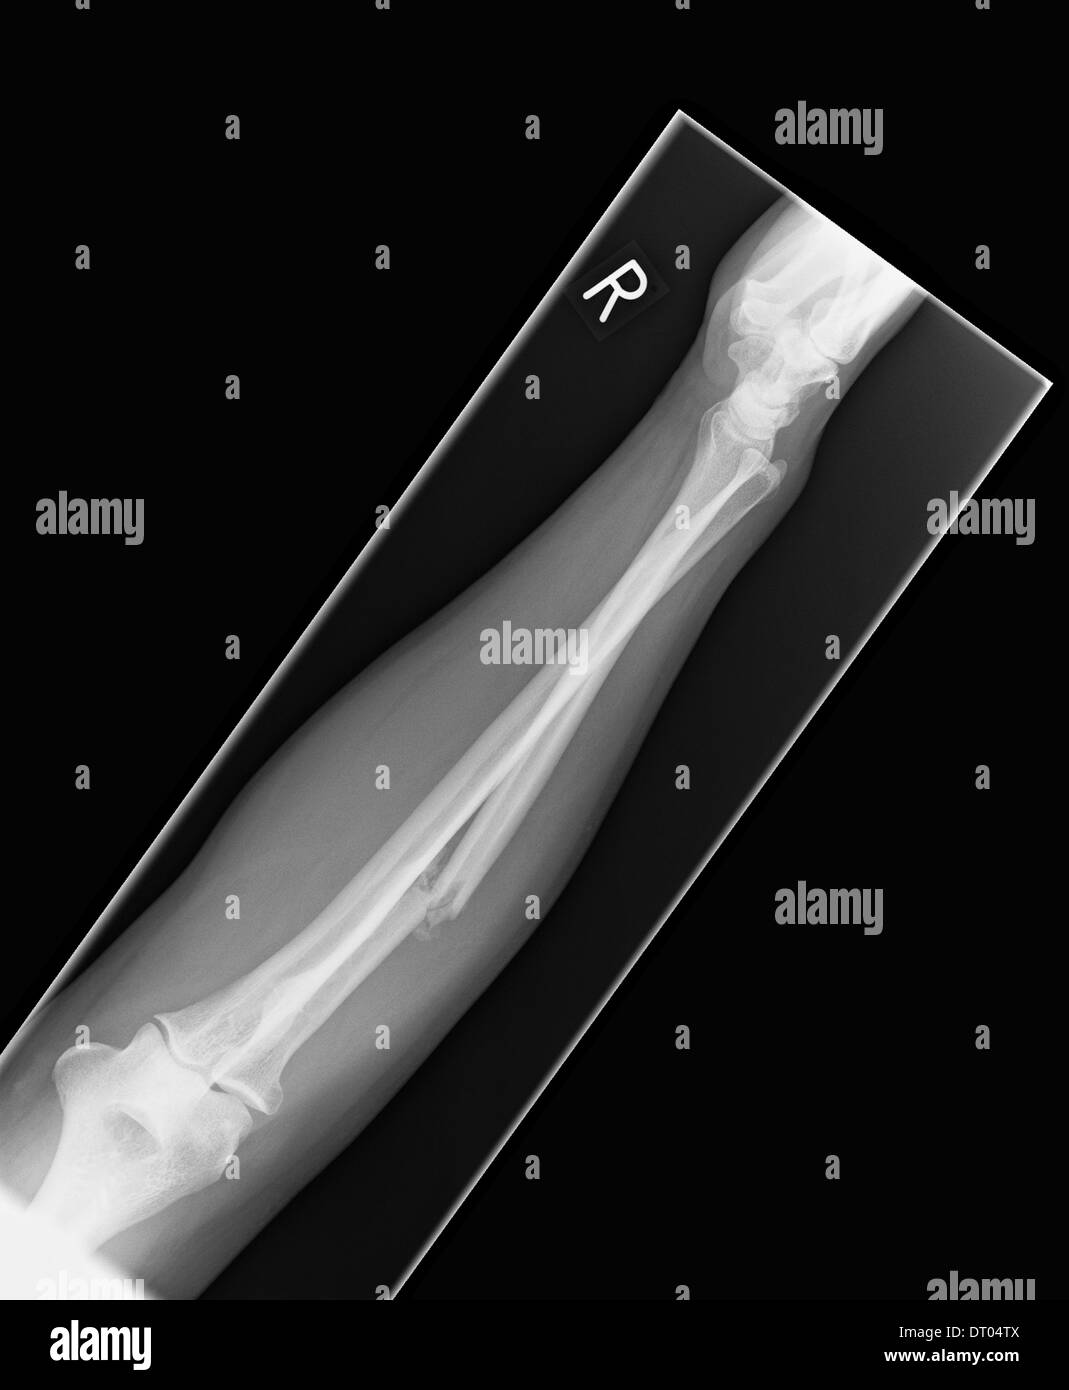

Distal radius and ulna fractures, Xray Stock Image C056/4213

Comparative Xray of human forearms displays fracture of the right Radius Bone Fracture X Ray Your fracture is not displaced, meaning it is in a good position, and should heal well if the advice below is followed. What is a distal radius or wrist fracture? It is important to assess the radiograph for a joint effusion and where one exists, to take extra. Radial head fractures can be subtle and easily missed on radiographs. The. Radius Bone Fracture X Ray.

Xray of human right forearm displays fracture of the radial bone Stock Radius Bone Fracture X Ray In the elderly, osteoporotic fractures of the distal radius are common. The process of healing is different depending on the configuration of the fracture fragments and can be divided into three main categories: It is important to assess the radiograph for a joint effusion and where one exists, to take extra. It is a break in one of the long. Radius Bone Fracture X Ray.